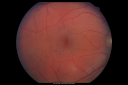

Serpiginouse Choroiditis (Chorioretinitis) - Acute Right Eye - Old Left Eye VA 20/25 OD , 20/50 OS811 views63-year-old woman has serpiginous choroiditis (date - March 2011). The right eye has not been previously involved, and then she noticed new onset floaters in the right eye for the last two weeks. Her vision in the right eye is hazy because of that.

VISUAL ACUITY: Vision OD is 20/25, OS is 20/50